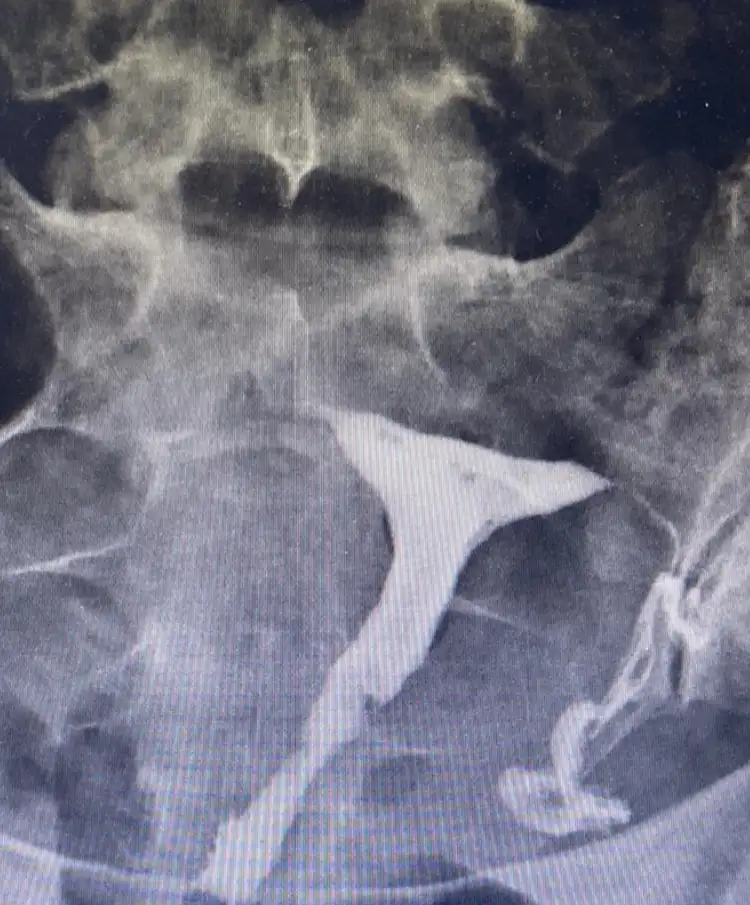

Kızlar hsg çekildim bugün ve tüplerimin tıkalı olduğunu öğrendim doktorla henüz detaylı konuşmadık ama çok kötüyüm duyduğumdan beri ağlıyorum kendimi mahvolmuş hissediyorum. Tüp bebek dışında hiç bir şekilde hamile kalamayacağım o kadar kötüyüm ki

Bakacağım numarasına eskişehirdeyim ama gerekirse görüşürüm tabi. Hsg de zaten ilaçlı su verilmiyor mu anestezili oldum ben ve doktorum açmaya çalıştığını ama tıkalı olduğunu söyledi. Aslında çok detaylı konuşamadık. Teşekkür ederim desteğin için. Ben yapışıklık varsa açılır diye düşünürken uyandığımda ikisinin de tıkalı olduğunu öğrendim çöktüm çok kötü oldum 😞

Daha önce bir ameliyat vs geçirdin mi canım? Dur bakalım hemen üzülme açma yöntemleri vardır iyice araştırmak lazım bir doktorun sözüyle kendini harab etme

Yaa böyle birşey beklemiyordum açıkcası açılma şansı yok muymuş açılıyor bazen o salınan sıvıyla ama bilemedim yaa üzüldüm 😒 böyle haber vereceğini düşünmemiştim dün konuşurken 🤔az doktorla konuş bakalım ne diyecek. 🙏🏼